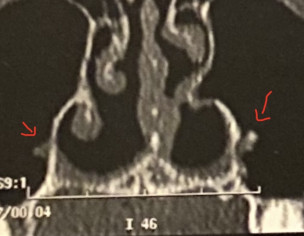

Hello Dr, I have pain in my nose after rhinoseptoplasty (a lot of grafts were placed), I want to know regarding the scan, what are the spurs pointed with a red arrow? Could it provoke pain? I also would like to know if the second image show scar tissue in my sinus or something else I know I have a synechia that I will need removed because it's causing congestion.. Thank you in advance